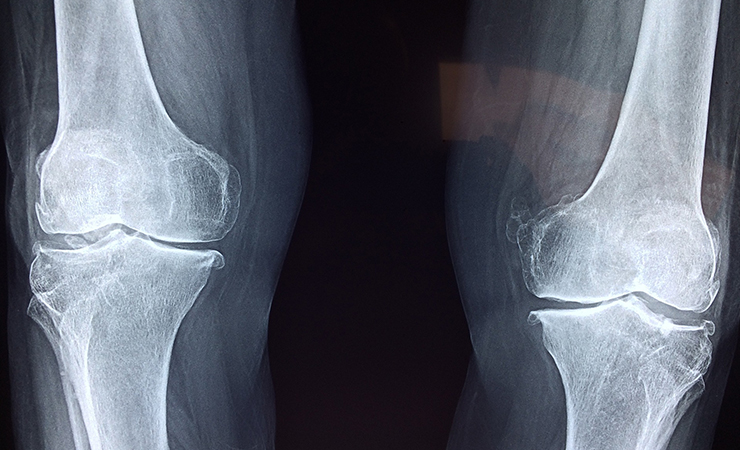

4. 정형외과

정형외과는

외과 계열 진료과목 중 하나로,

뼈와 관절을 중심으로

근골격계에 통증이나 이상이 생겼을 때의

질환을 취급하는 외과입니다.

- 정형외과 증상 -

✅ 골절

✅ 관절의 경직, 통증, 뻐근함

✅ 손가락, 손, 발, 손목, 발목의 통증

✅ 목 관절 통증과 어지러움

✅ 뼈가 틀어져 교정이 필요할 때

✅ 근육, 인대에 문제가 생겼을 때

✅ 담 걸렸을 때

✅ 척추측만증

✅ 족저 근막염